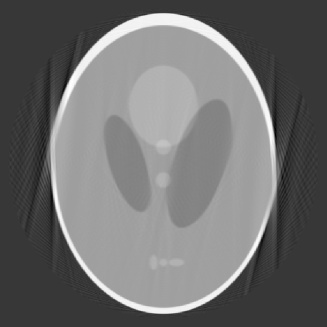

In our next example, we consider the case , which means that the data is limited to views with angles distributed over an arc of . The reconstruction with and is given in Figure 4.

In this image, artifacts and distortion are clearly visible and most prominent at two points on the edges of the images. The maximum of the conditional numbers in this case is merely 503, so that the matrices are in fact fairly well conditioned. This suggests that the distortion is likely caused by the choice of , which means that no polynomial preservation is kept.

4.2. Data with noise

The limited angle problem is well known to be ill-posed. Below we present our reconstruction with noise data. We use again the Shepp-Logan head phantom but add noise in the data, which is Gaussian normally distributed with zero mean and a standard deviation 0.03. The noise is about 2% in the data. For limited angle, we choose and , respectively, which correspond to data limited over an arc of and , respectively. The reconstructed images by our algorithm with and are given in Figure 5.

These reconstruction should be compared with the left image in Figure 3 and the image in Figure 4, respectively, which are the reconstructed images based on the same limited angle data but without noise. These images indicate that our method is relatively stable, in the sense that the reconstructed images are not distorted much by the noise.